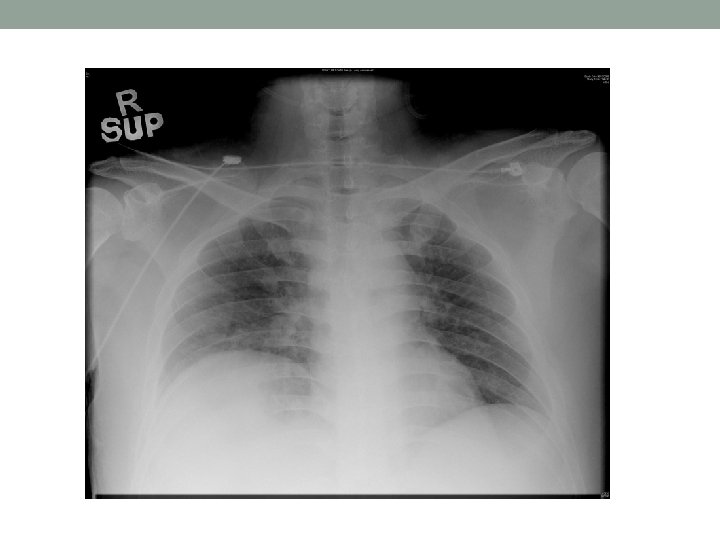

Day 2 • CXR: Rt middle zone consolidation • Antibiotics: • To rocephin and stat dose amikan(750 mg) right after deterioration • Added azithromycin after obvious consolidation shown • Tazocin after blood C/ST: GNB